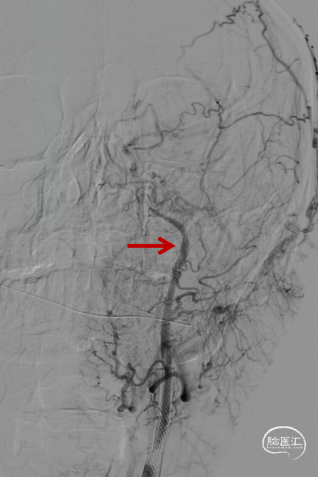

等待10分钟,复查造影颈内动脉及远端分支通畅,结束手术。DynaCT左侧外囊区域少许造影剂渗出。

术后4h复查CT示渗出消失,左侧额叶导叶低密度灶。

术后第三天MRI示左侧额叶及导叶梗死,MRA血流通畅。患者症状明显缓解,NIHSS评分2分。